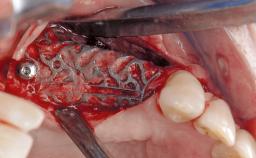

Reconstructive Treatment of a Peri-Implantitis Defect at an Implant in a Mandibular Molar Site

In this case, Mario Roccuzzo utilizes surgical bone regeneration treatment around implant 46 using a bone graft substitute and a connective tissue graft to resolve peri-implant inflammation, reduce the probing depths, and prevent further progression of disease.